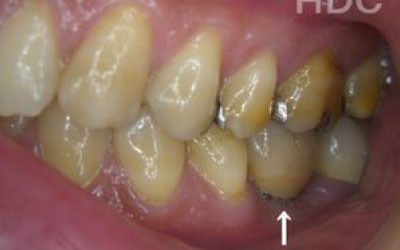

3 歯周病でインプラントが抜けるリスク

細菌(歯垢)によって、支えとなる歯茎や骨が衰えることがあります。

つまり、インプラント治療だけでなく、残っている歯の歯周病の検査や治療も非常に重要です。